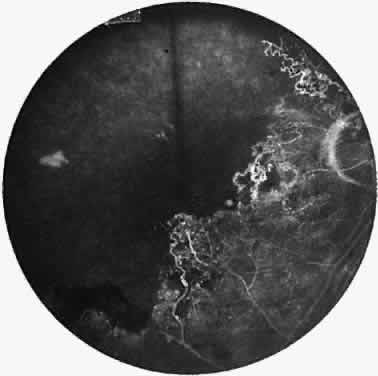

Elliot and Spitnas and colleagues have documented the abnormalities at the junction between the anteroperipheral nonperfused and the posterior perfused retina.9,10 Intraretinal hemorrhages often first appear in the affected area, followed by an increase in vascular tortuosity with frequent collateral formation around occluded vessels (see Fig. 3). Microaneurysms, arteriovenous shunts, and venous beading are commonly seen at the junction (Fig. 4). Fluorescein angiography enhances these abnormalities and often demonstrates staining at the stumps of obliterated vessels.

Fig. 4. Fluorescein angiogram demonstrating severe nonperfusion involving the macula. In this case, the macular nonperfusion was responsible for loss of central vision.

As a result of the retinal nonperfusion, new vessels can form either on the disc (neovascularization of the disc) or, more commonly, neovascularization can occur elsewhere in the retina (Fig. 5). These abnormal blood vessels can hemorrhage and are the major cause of visual loss in this disease. The neovascularization in the peripheral retina usually occurs at the junction of perfused and nonperfused retina, similar to the appearance of neovascularization in the peripheral retina in diabetic retinopathy and the other peripheral proliferative retinopathies. Neovascularization can be associated with extensive fibrovascular proliferation and fibrosis (Fig. 6). The anteroposterior and tangential traction resulting from the fibrovascular proliferation places these eyes at risk for development of retinal detachment. Neovascularization of the iris also has been described.

Fig. 5. Neovascularization of the peripheral retina has developed at the junction of perfused and nonperfused retina.